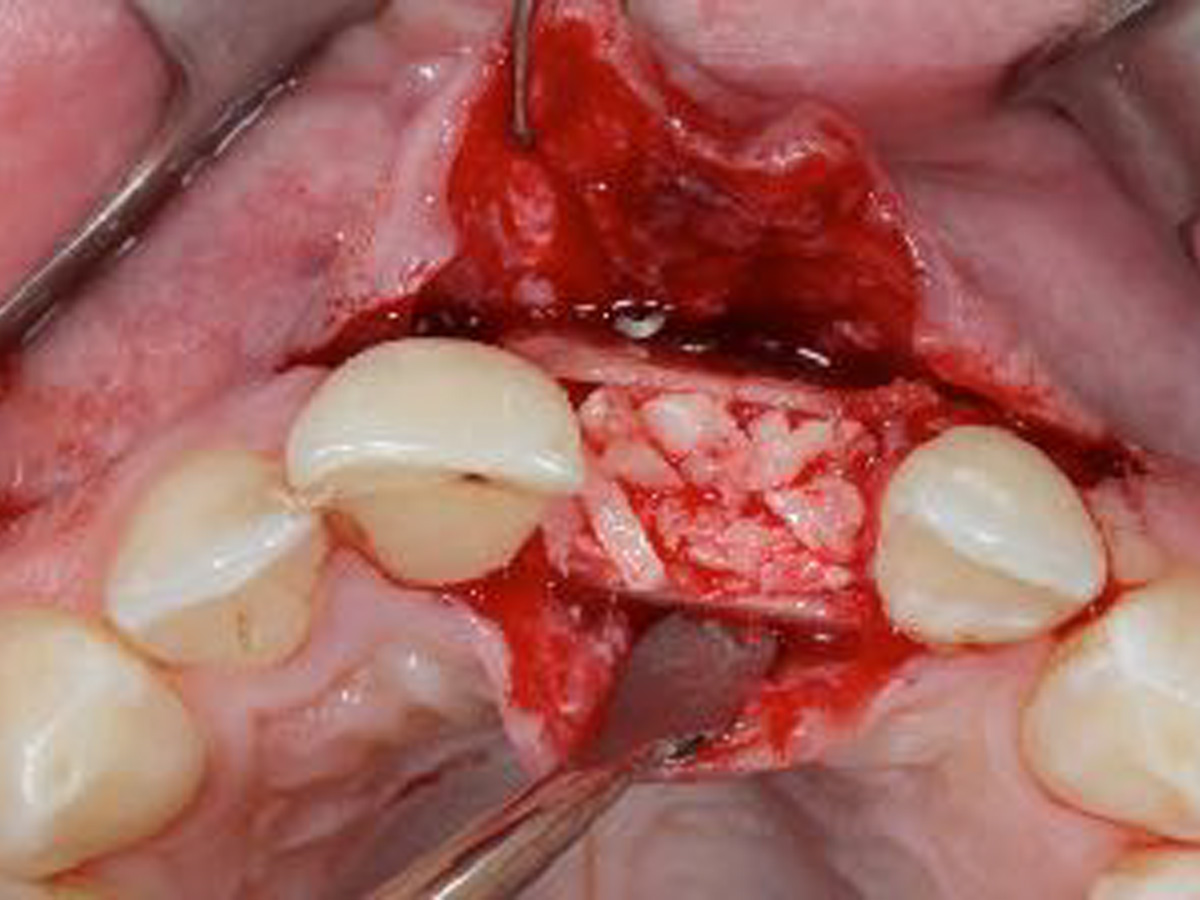

Vertikale Augmentation im ästhetischen Bereich

Autor: PD Dr. Arndt Happe